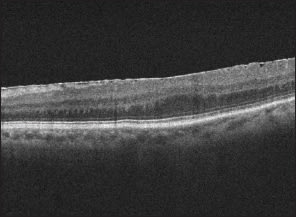

Optical coherence tomography has quickly become a mainstay of retinal imaging for ophthalmologists. OCT systems are based on the principle of interferometry, which is similar to ultrasound except that near-infrared light (810 nm) replaces sound as the medium that is reflected as backscatter to create an image.8 Initially, OCT images were captured with time-domain OCTs (TD-OCT) but the next iteration came soon after with spectral-domain devices (SD-OCT). They provide sharper resolution of retinal layers and faster image-capture speeds than time-domain, and have found increased adoption in clinical practice. Recent research has lead to the advent of the novel frequency-domain OCT (FD-OCT) devices, which provide yet another significant improvement in resolution and speed.

SD-OCT differs from its predecessor because of its use of the Fourier mathematical transformation, which can sum a single periodic function into a series of sinusoidal functions. Once applied to the OCT, the Fourier transformation allows the simultaneous measurement of light reflection in the SD-OCT, compared to the sequential measurement in TD-OCT. The net result is an improvement in resolution of images from 10 µm to 1 µm, which has allowed detection of small cystic changes such as those seen early in the pathogenesis of wet AMD.9 The FD-OCT, though not yet available for widespread use, may well have the broadest application in clinical practice of the three OCT systems. Whereas SD-OCT uses a broadband light source and a spectrometer, the FD-OCT utilizes a wavelength-swept laser source. This change allows an improvement from the 40 kHz readout rates of the SD-OCTs to repetition rates as high as 370 kHz in the FD-OCTs. Clinically, the potential of the FD-OCTs is vast because of their wide fields of view, and they have found such far-reaching uses as imaging of coronary arteries and esophageal epithelium.10

3. Time-domain vs. Spectral-domain OCT

Advantages: User-friendly; less expensive.

Limitations: Lower resolution (10 µm); poor resolution of retinal layers; slower image capture; no eye tracking feature

Optimal Uses: Macular pathologies.

Advantages: Significantly improved resolution (1 µm); more images taken; eye tracking feature.

Limitations: More expensive; subject to inversion artifact.

Optimal Uses: Any cystic macular changes, ERM, VMT, following response to anti-VEGF agents.

4. Epiretinal Membrane: OCT vs. Digital Fundus Photo

Most Optimal Technique

Advantages: Comparative measurements of progression; better analysis of complications with macular pucker and macular hole.

Limitations: Cannot see entire extent of surface over which puckering may occur.